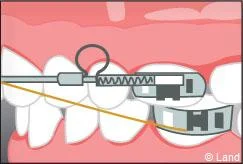

Ils sont associés aux bagues et peuvent venir compléter et renforcer l’efficacité de l’appareillage fixe. Il existe des élastiques ou de ressorts qui peuvent aider au déplacement des dents en complément du fil, en servant de guide et des forces extra-orales portées la nuit qui agissent sur des secteurs osseux plus étendus.